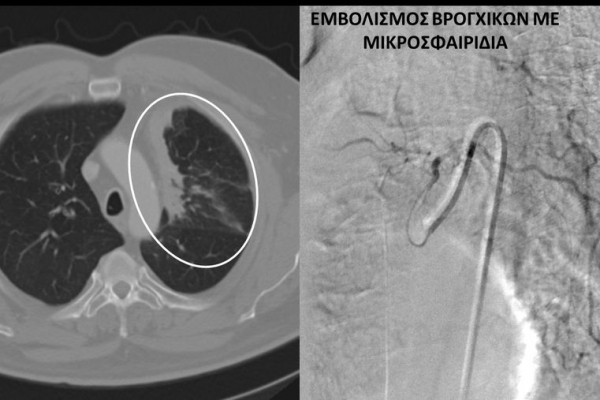

Υποτροπιάζουσα αιμόπτυση

Συνοπτικά υπό την καθοδήγηση του αγγειογράφου, αναγνωρίζεταιτο παθολογικό αγγείο-αγγεία και με ειδικούς καθετήρες και μικροκαθετήρες, διοχετεύονται εμβολικά υλικάόπως μικροσφαιρίδια ή coils, ώστε να αποφραχθεί ή να μειωθεί η παθολογική αγγείωση.